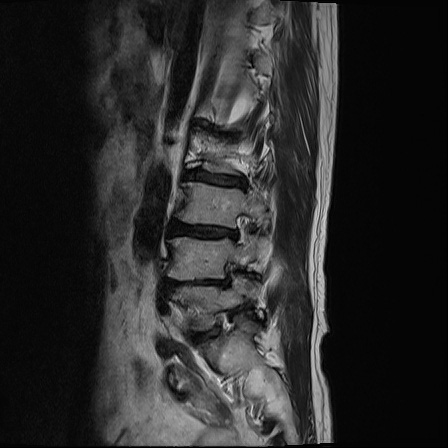

Ӵϲ ɿ ô ô 㸮 ٸ ̾ϴ. ϵ Ͻð ܻ 㸮 20⵿ ͽϴ. mri ˻ ɿ Ȳ ʹ ؼ Ȳ̶ ߽ϴ. ϻȰ ϰ 鼭 ½ϴ. ̴ ø鼭 Ͻô Ȳ ̷ ġ ص ȸ ϴ. δ Ҵµ, ù ȸԲ ˷ֽ ϰ β ϰ, ˷ֽ ü ƮĪ ϸ鼭 ȭǸ鼭 Ӵϲ ȸų ְ ǰ, β 鼭 ʴ β ؾϴ ŷο 1ϸ ijħ ڸ ǥ Ʈ ߽ϴ. ȸ ȭϽø鼭 Ϸ簡 ٸ ȸǽð 4ְ Ǿ Ǯ鼭 ¦ ҽϴ. ħ ȸ ȭϸ鼭 ڼ ü ƮĪ ϴ. ȥڼ Ͻʴϴ. ٳø鼭 ó Ͻ ʴϴ. ̾ ְ ̳ ߵ ʰ ϴ ȸԲ Ͻʴϴ. ʹ ϸ鼭 ϴ. Ȩ - ϱ ٴ Ȳ MRIԴϴ. |